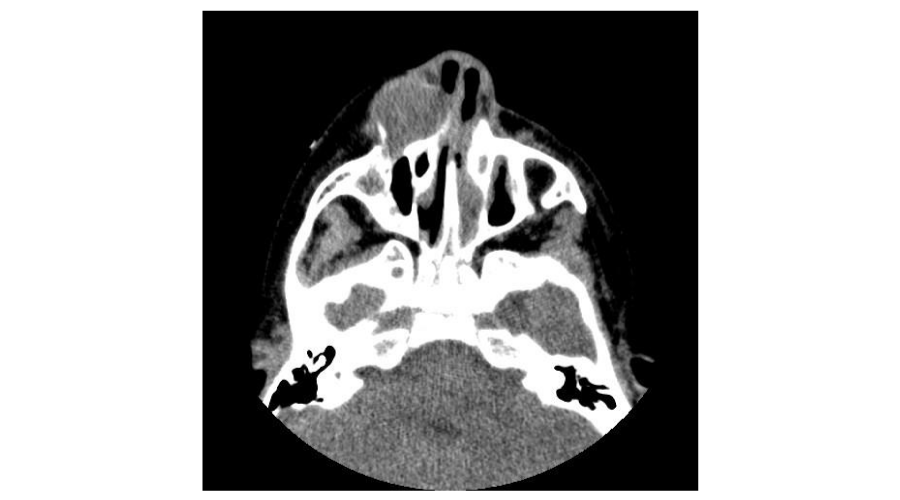

In CT-scan examination there was a low-density lesion arising within the anterior medial aspect of the left maxillary bone with erosion of the maxillary sinus and the lateral nasal wall (Figure 1). There was separation of the mass from the nasal-lacrimal duct. Taking into account the history of trauma to the area, the CT scan concluded that the lesion was compatible with post-traumatic cyst.

Figure 1: